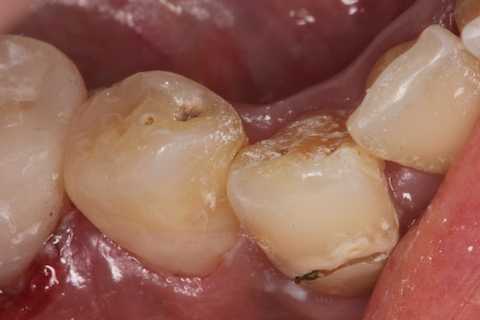

残根上のCR8 2025.10.28